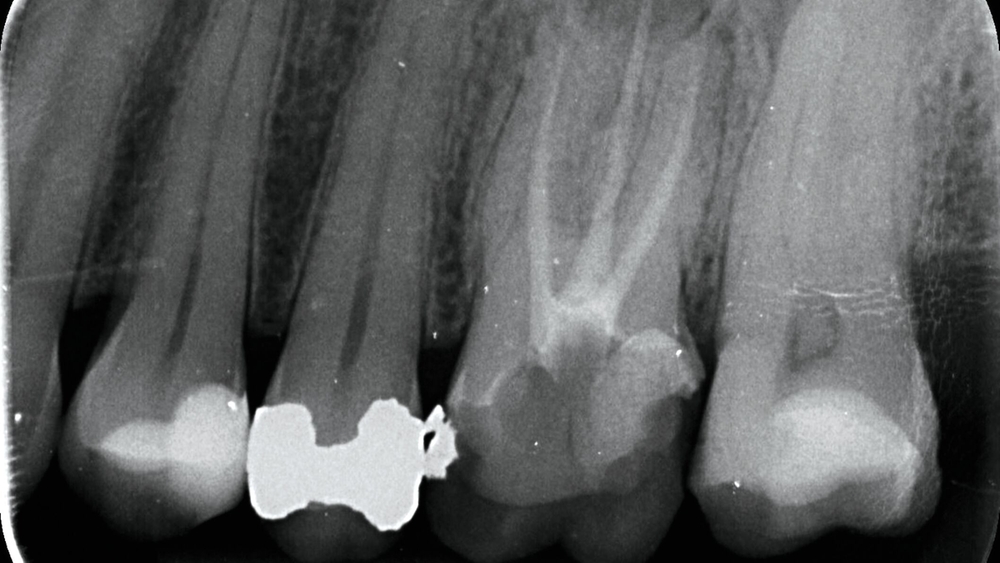

Im Februar 2022 stellte sich die 46-jährige Patientin nach Überweisung durch die Hauszahnärztin mit seit zwei Wochen bestehenden Schmerzen im linken Oberkiefer in einer MKG-chirurgischen Praxis vor. Klinisch und radiologisch zeigten sich eine tiefe Karies an Zahn 26 mit apikaler Ostitis und enger Beziehung zur Kieferhöhle (Abbildung 1) sowie der devitale Zahn 27.

Zwischen März und Oktober 2022 erfolgten dort eine Wurzelkanalbehandlung und später eine Revision an Zahn 26 sowie eine Trepanation von Zahn 27 mit Abfluss von putridem Sekret. Trotz dieser Maßnahmen blieben die Beschwerden bestehen. Ein DVT im Mai 2023 zeigte eine zystische Läsion in regio 27 mit Verdacht auf Kieferhöhlenperforation und bereits vollständiger Verschattung der linken Kieferhöhle (Abbildung 2). Zahn 27 wurde daraufhin extrahiert.

Dieser Fall demonstriert die Herausforderungen und Schwierigkeiten bei der Differenzierung zwischen odontogener und rhinogener Sinusitis. Trotz dentalem Fokus dominierte die Einschätzung einer primär rhinogenen Ursache für die Sinusitis – nach vermeintlicher Sanierung des odontogenen Fokus. Die recht kleine Fistelung war in den konventionellen Röntgenaufnahmen nicht eindeutig erkennbar, der odontogene Fokus wurde durch die MRT-Aufnahme hervorgehoben.